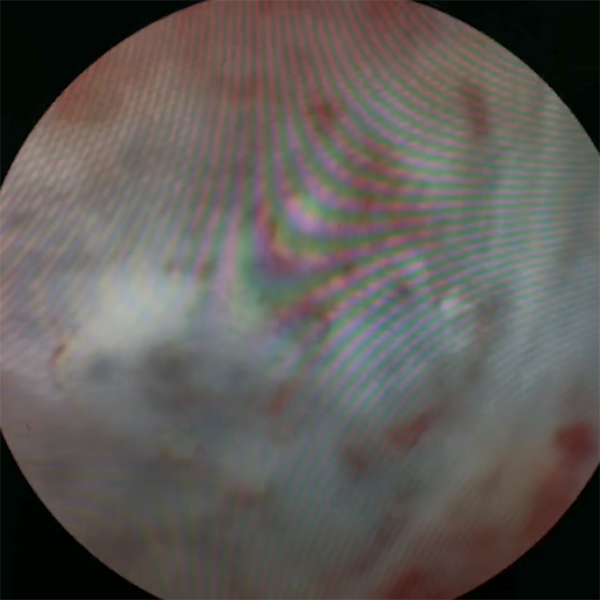

宫腔直视人流术是一种新型的无痛可视人流技术,通过在吸引管前端集成超微型高分辨率摄像头,实现手术过程中对宫腔内情况的实时、同步、全程直视观察,从而提高手术的精准度和安全性。

高清镜头可清晰显示孕囊位置、大小及宫腔环境,实现了宫腔的实时、同步、全程观察。吸引管能准确找到目标,一步到位吸除孕囊和蜕膜组织。